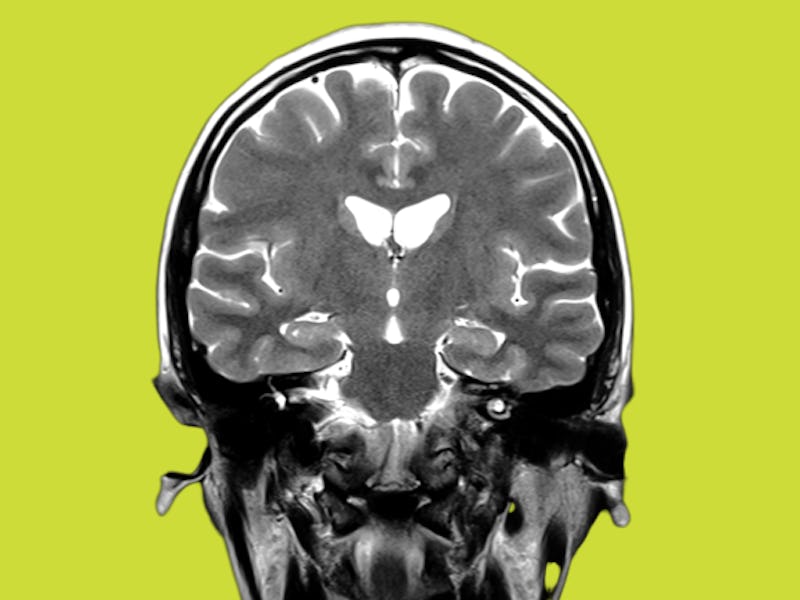

Brain images of infected mice showed infection of the substantia nigra (an important structure for movement), and ventral tegmental area (the area of the brain responsible for dopamine production and circulation). Loss of dopaminergic neurons (neurons, or signal-transducing brain cells that transmit dopamine) are also a hallmark sign of Parkinson’s-like disease progression.